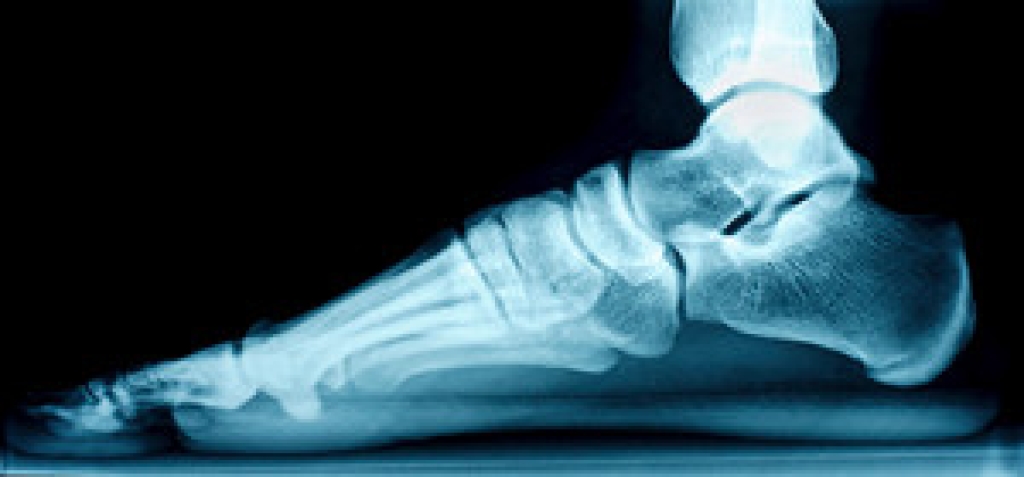

Flat feet are a common condition in which the feet lack a visible arch in the sole when weight is placed on them. There are several telltale signs of flat feet. The first is overpronation, an abnormal gait in which your feet roll inwards when you walk. If you have an overpronated gait, you may notice that the soles of your shoes wear more quickly along the inner border. Other signs of flat feet include having feet that point slightly outward when you walk or stand, pain in the joints of your lower limbs, hips, and lower back, and pain in the arch of the foot. If you are experiencing discomfort due to flat feet, please see a podiatrist for treatment.

Flatfoot is a condition in which the arch of the foot is depressed and the sole of the foot is almost completely in contact with the ground. About 20-30% of the population generally has flat feet because their arches never formed during growth.